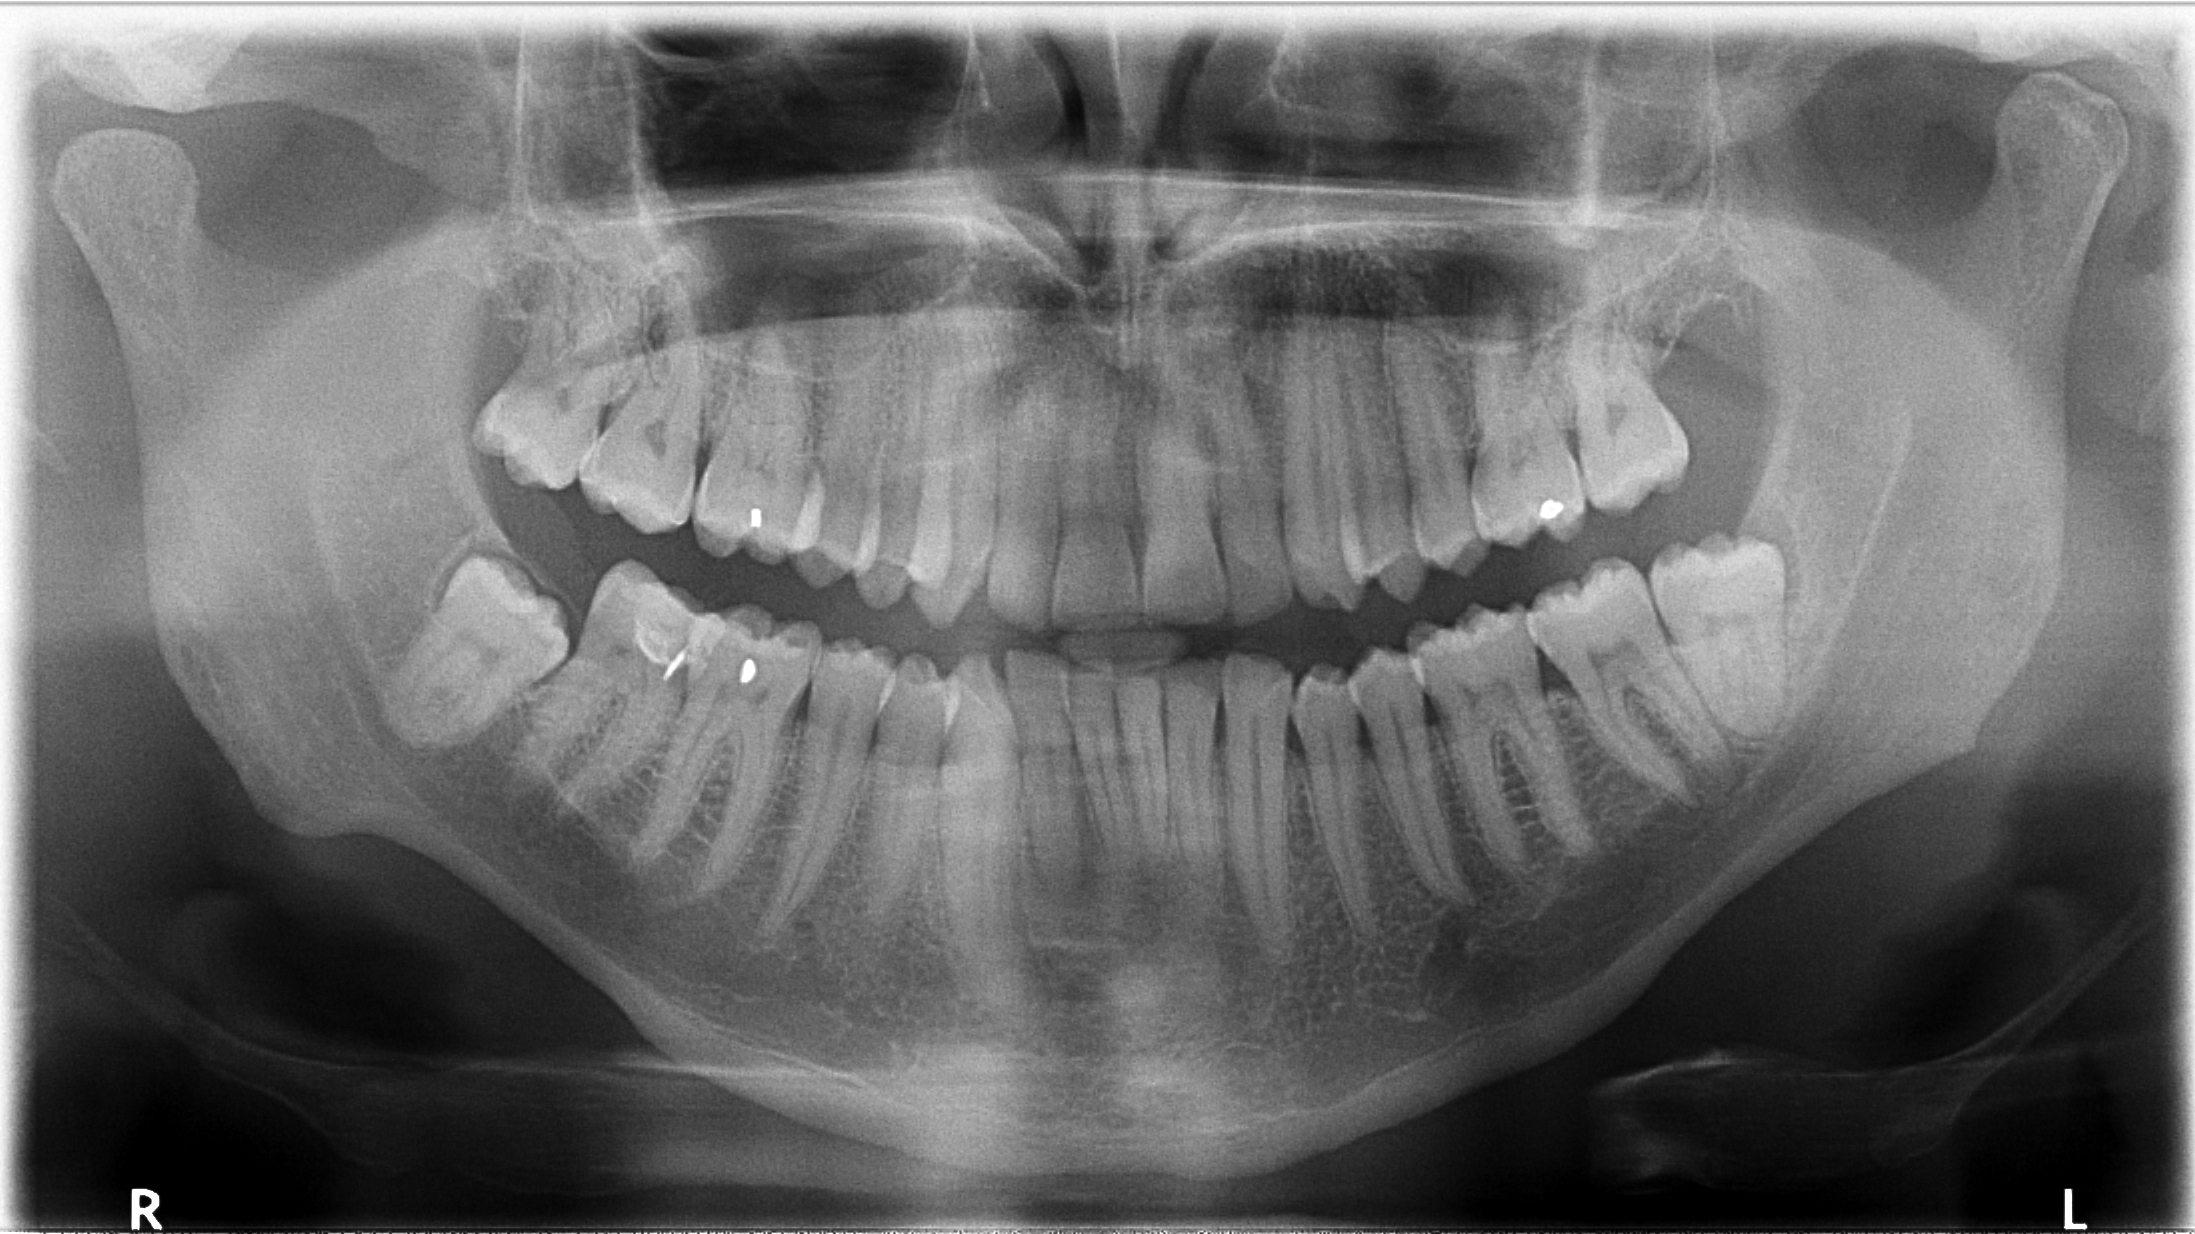

Periapical X-rays show the entire tooth, from the crown to the root, and can diagnose issues such as abscesses, cysts, or impacted teeth (see Figure 15). Bitewing X-rays are used to detect cavities between teeth, to evaluate the health of the teeth and gingiva, and to evaluate periodontal bone loss caused by gingival disease (see Figure 16). Panoramic X-rays provide a broad view of the entire mouth, useful for assessing the position of teeth, especially wisdom teeth, and detecting tumors or other abnormalities (see Figure 17).

Figure 17. Panoramic X-Ray |

![]() |

Source: Getty Images |

Cone beam computed tomography (CBCT) is a 3D imaging technique that provides detailed views of bone and soft tissues, helpful for complex cases and implant planning. Children and teenagers require more frequent X-rays to monitor tooth development. A history of extensive decay, gum disease, or other dental issues may necessitate more frequent X-rays. Factors such as smoking, dry mouth, or diabetes can increase the risk of oral health problems, potentially requiring more frequent X-rays. The frequency and type of dental X-rays depends on individual needs, with general guidelines varying based on age, oral health, and risk factors.